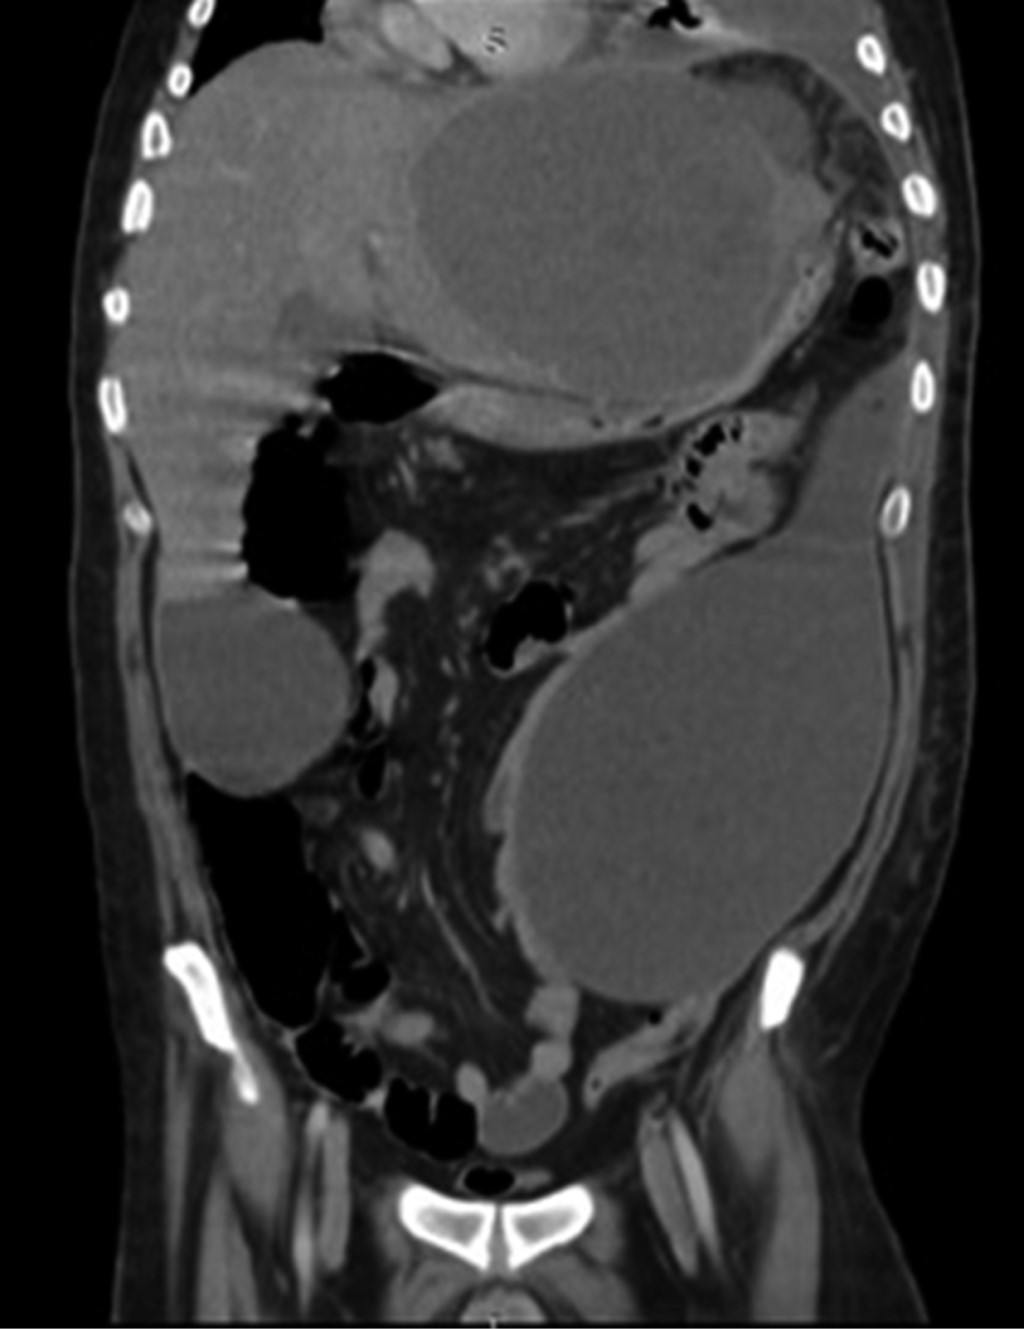

Se realizó una radiografía anteroposterior (AP) de tórax, en la cual se visualizó un derrame pleural izquierdo que cubría más de 50%. La tomografía computarizada mostró una importante cantidad de líquido en el espacio pleural izquierdo que condicionó una atelectasia pasiva del lóbulo inferior (Figura 1); el hígado se encontró con densidad heterogénea con incremento del lóbulo hepático izquierdo secundario a la presencia de una lesión heterogénea hipodensa con bordes lobulados, que muestra un reforzamiento periférico y de algunos septos internos, la cual abarca los segmentos II, III, IVa y IVb midiendo aproximadamente 20 × 14.5 × 12.5 cm (Figura 2), condicionando desplazamiento posterior y compresión del estómago y del páncreas y desplazamiento caudal de las asas intestinales (Figuras 3 y 4). En el polo inferior del lóbulo hepático derecho adyacente al segmento IV se identifica una lesión de aspecto quístico homogéneo con reforzamiento periférico tras la administración de contraste intravenoso, midiendo en sus ejes mayores 25 × 27 × 13 cm. Como manejo inicial se le colocó una sonda Foley y sonda nasogástrica presentando gasto de características gástricas (30 ml). Se colocó un catéter central, verificado por radiografía. Se solicitaron estudios de imagen. Se le indicó ayuno, se inició fluidoterapia, antibioticoterapia con ceftriaxona y metronidazol, manejo del dolor, control glucémico y protector gástrico. Al visualizar la imagen del derrame pleural izquierdo, se decide realizar una toracocentesis, obteniendo exudado espeso de aspecto "chocolatoso". Al momento de contar con la tomografía se inicia tratamiento quirúrgico urgente.

Figura 3

Figura 4